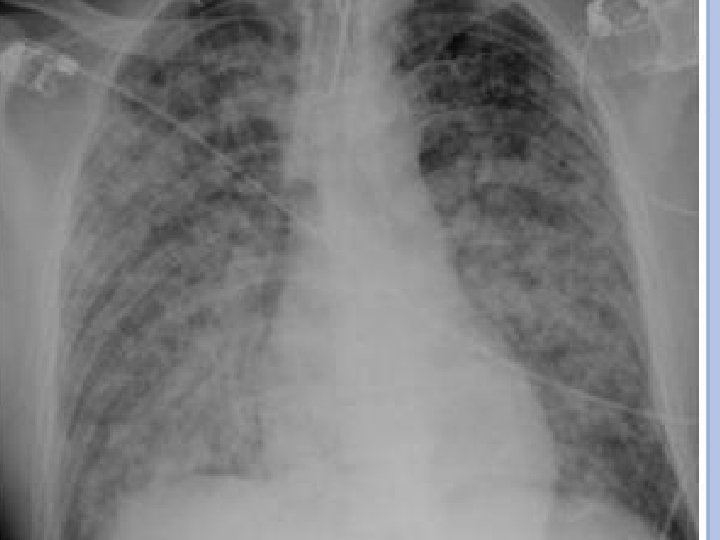

COMPLICAÇÕES PULMONARES Pneumonia viral: Ocorre 1 -6 dias após o início do exantema. Rx de tórax: infiltrados intersticiais, nodulares, presença de derrame pleural etc. QC: tosse, taquidispneia, cianose, dor pleurítica e hemoptise. É rara em paciente imunocompetente! Pneumonia bacteriana: Principal causa de óbito em crianças com varicela! QC: febre persistente após 3 -4 dias do início do exantema com tosse e dispneia.

COMPLICAÇÕES DO CASO CLÍNICO A internação foi bem indicada: Presença de complicação sistêmica (infecção bacteriana 2ª de pele + pneumonia). Risco de infecção 2ª durante a doença: Complicação mais comum (5%). Este caso teve complicação: Quadro habitual é benigno e autolimitado.